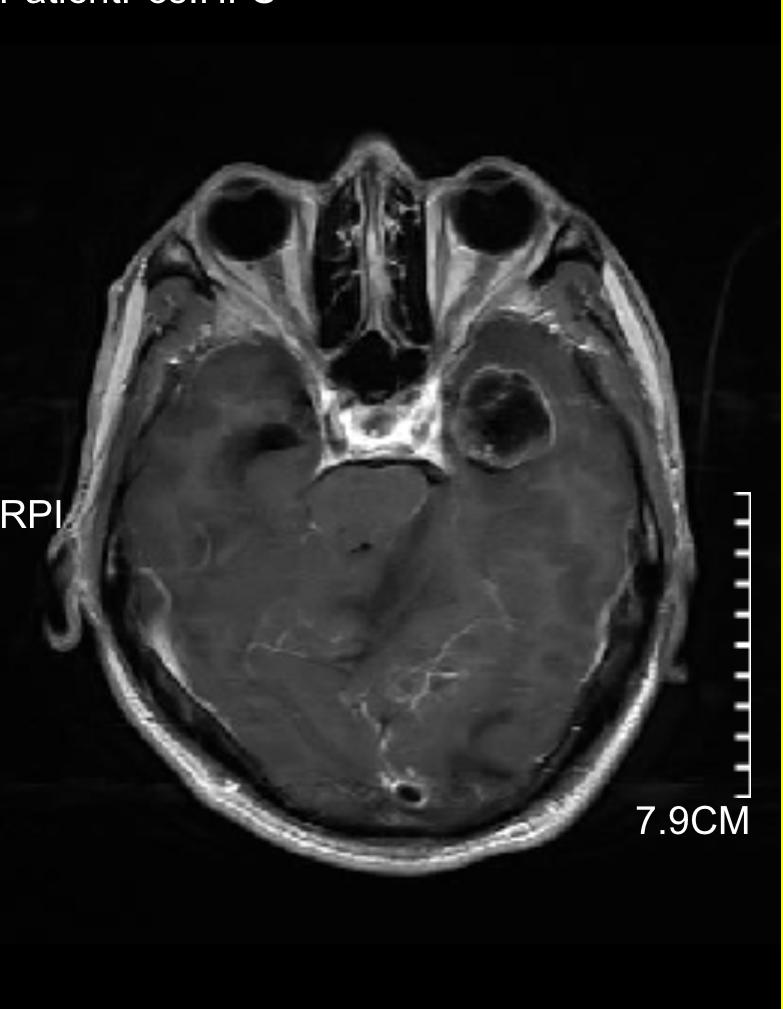

下图的病例是一个以头痛、行走不稳为主要表现,查头颅磁共振发现颅内三个大的转移灶,同时肺部发现巨大肿瘤,脑内病灶给予全部切除,术后根据基因检测结果进行化疗及靶向、免疫治疗。

颞部巨大转移瘤

颞部转移瘤已切除